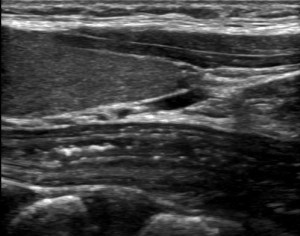

esoph 2